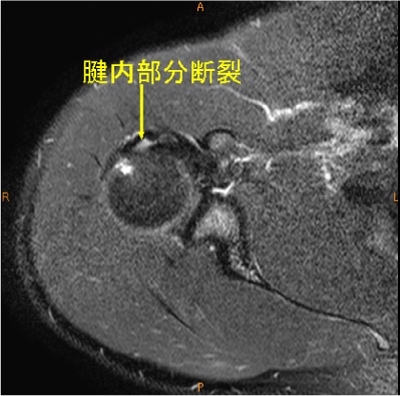

MRI所見

腱内の所見は脂肪抑制T2WIでないと描出するのが難しい。

棘上筋腱停止部腱内の剥離, 腫脹著明, AC-jointのOA